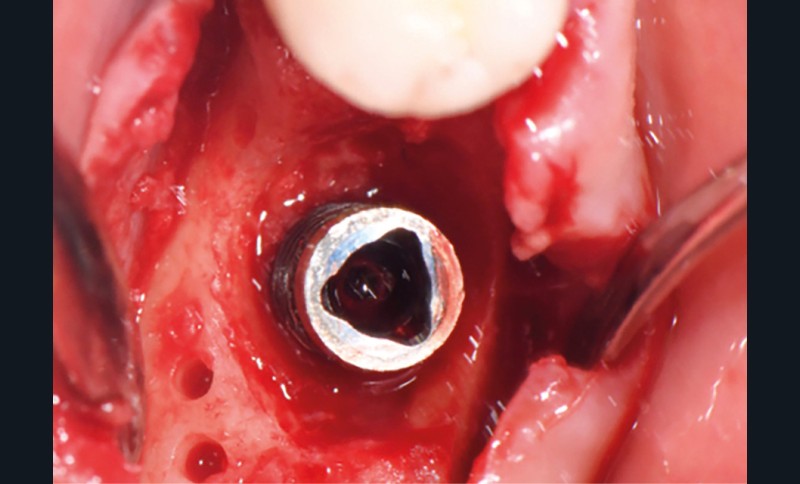

- Péri-implantite sur l’implant 47, diagnostiquée en août 2022

- Implant posé en 2017

- Nobel Replace Select RP (4,1 x 10 mm)

La couronne a été déposée et une vis de couverture mise en place. La patiente a reçu un nettoyage supra-gingival général avec une attention particulière pour l’implant 47, et une irrigation locale avec du gel de chlorhexidine et du peroxyde d’hydrogène pour réduire l’inflammation des tissus. De l’amoxicilline (3 x 500 mg) a été prescrite, à commencer la veille de l’intervention chirurgicale.